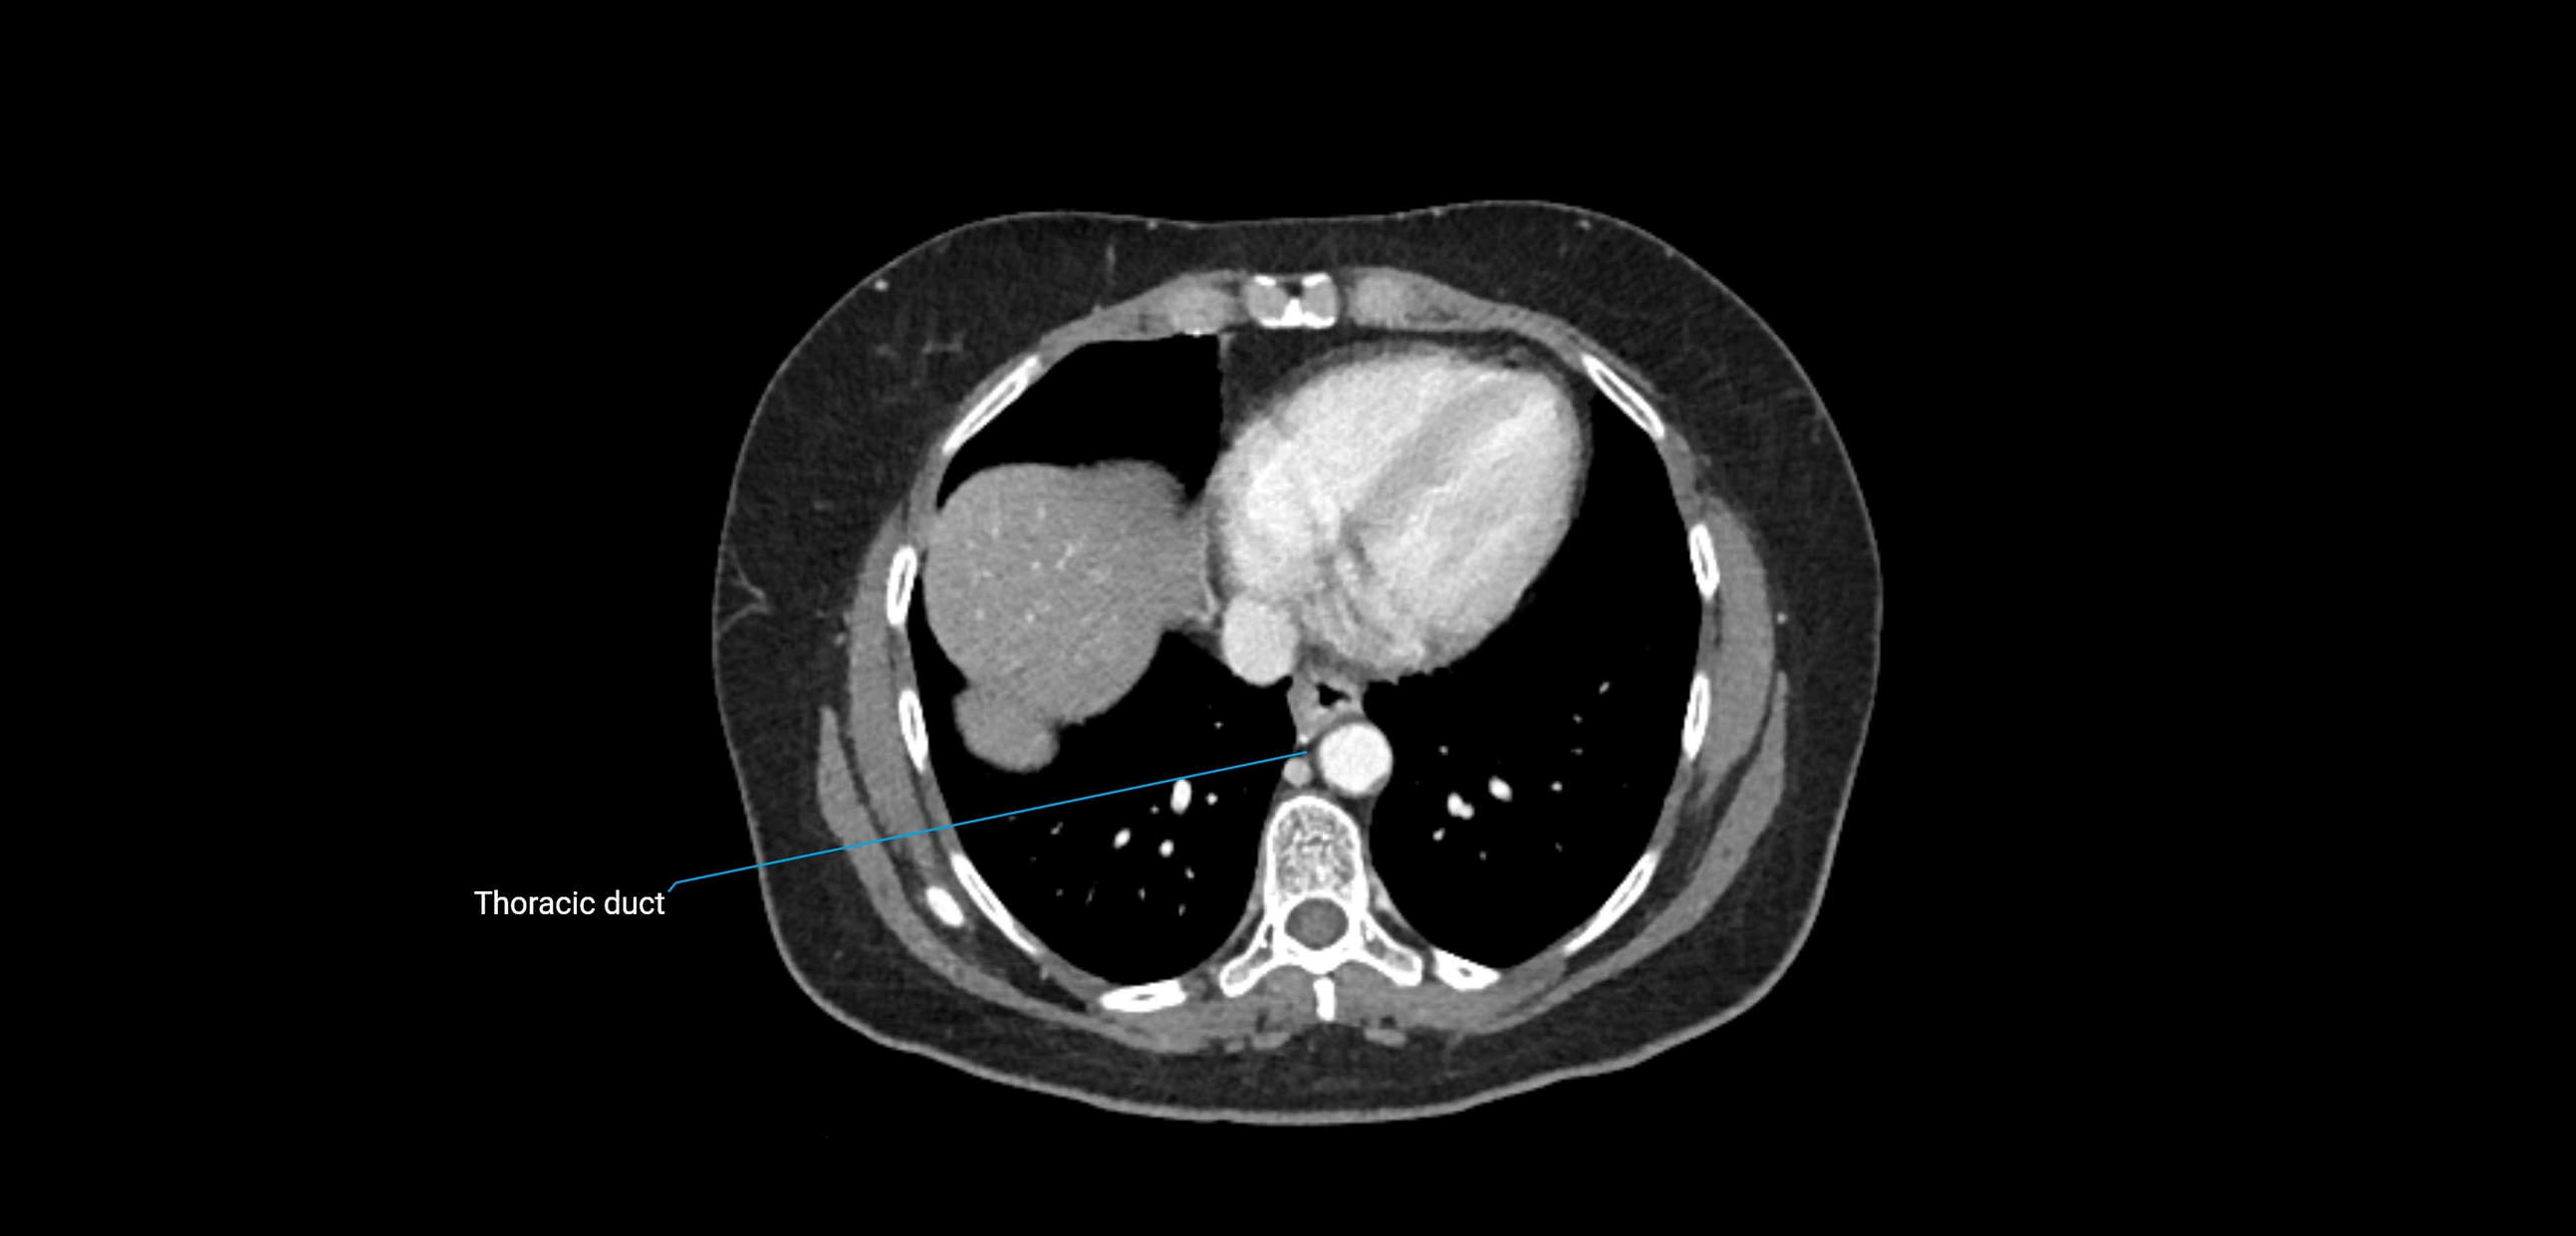

CT Appearance

CT Post-Contrast:

• Normal nodes enhance homogeneously

• Malignant nodes may show heterogeneous enhancement, central necrosis, or conglomerate formation

CT Venography (CTV):

• Demonstrates nodal encasement or compression of adjacent vessels (aorta, IVC, renal veins)

• Useful in staging testicular and ovarian malignancies

• Provides 3D reconstructions for retroperitoneal lymph node dissection planning